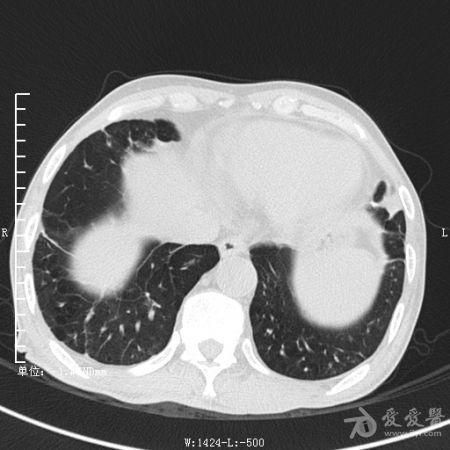

典型支气管扩张及肺水肿CT片

典型支气管扩张肺水肿